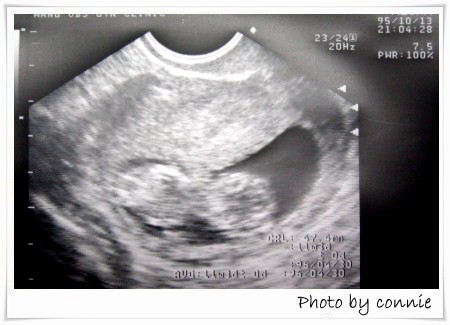

第二次產檢:

日期:95年10月13日

週數:11周+

血壓:138/88 (好像有點高..@@")

體重:-0.2